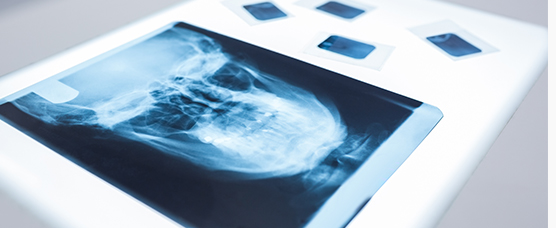

턱관절은 귀 바로 앞부분에 위치해 있으며,

두개골의 측두골과 하악골이 만나는 관절로 그 중간에는 섬유조직의

디스크가 위치해 있습니다.

턱관절은 다른 관절처럼 회전운동 뿐만 아니라

활주운동이라는 특유의 운동을 하는데 인체의 관절 중 가장 복잡한

구조를 지니고 있습니다.